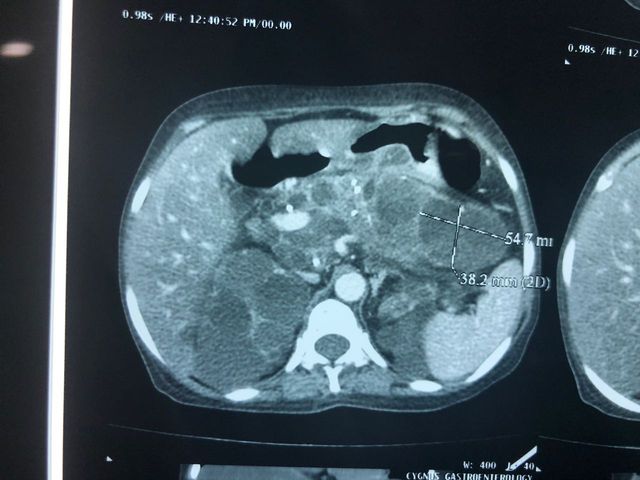

Cystic neoplasm of Pancreas

Middle aged female patient came with complaints of chronic upper abdominal pain since 6 months. The pain was mild to moderate, dull aching, non-radiating and not related to meals or defecation. It was not associated with vomiting, jaundice or abdominal lump. CT Abdomen suggested a cystic lesion in the distal body of pancreas of size 3x3 cm without communication with PD. Endoscopic Ultrasound guided Fine-needle aspiration (FNA) was performed and aspirated fluid suggested elevated CEA levels to 1168 with elevated amylase and lipase with mucin stain positive. Patient underwent laparoscopic spleen preserving distal pancreatectomy (Warshaw's technique). The resected specimen suggested mucinous cystadenoma of pancreas. The patient is asymptomatic now.